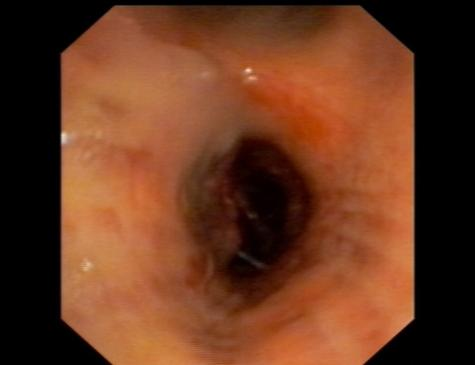

患者莫先生(化名)1个月前开始出现咳嗽、咳痰,并逐渐出现胸闷、憋气,走路时呼吸困难,且症状进行性加重。曾在多所医院就诊,但效果都不理想。经过朋友推荐,莫先生慕名前往自治区南溪山医院寻求帮助。在进行诊疗时,莫先生表现出轻微活动后即出现显著的呼吸困难,且在未吸氧状态下,其末梢血氧饱和度低于85%(正常范围应超过95%)。通过肺部CT扫描及支气管镜检查,发现其左侧主支气管被新生物阻塞,伴随有肺不张和严重的肺气肿,肺功能评估结果极差。

术前